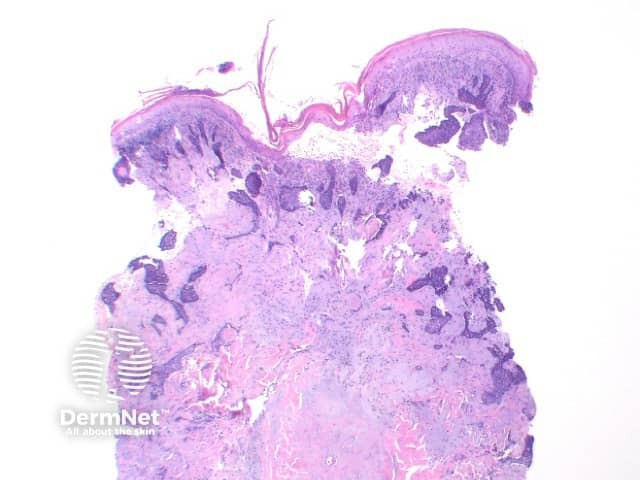

Superficial BCC: This variant show multifocal nests of atypical basaloid epithelium arising as buds from the basal layer of the epidermis. These nests remain confined to the papillary dermis (Figure 5)

Figure 5